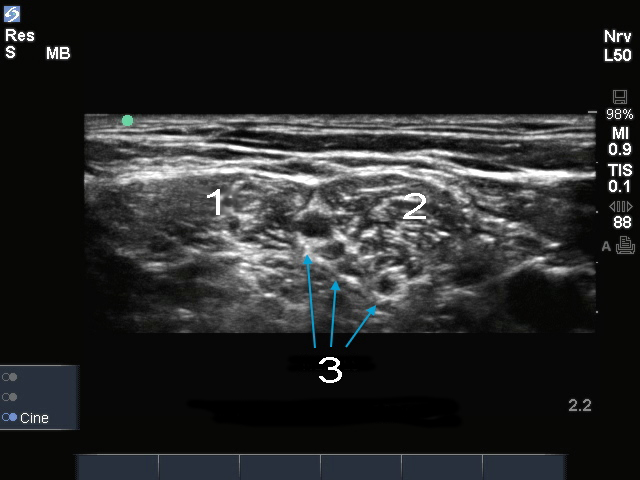

Edge:肌间沟神经

MSM

ASM

神经